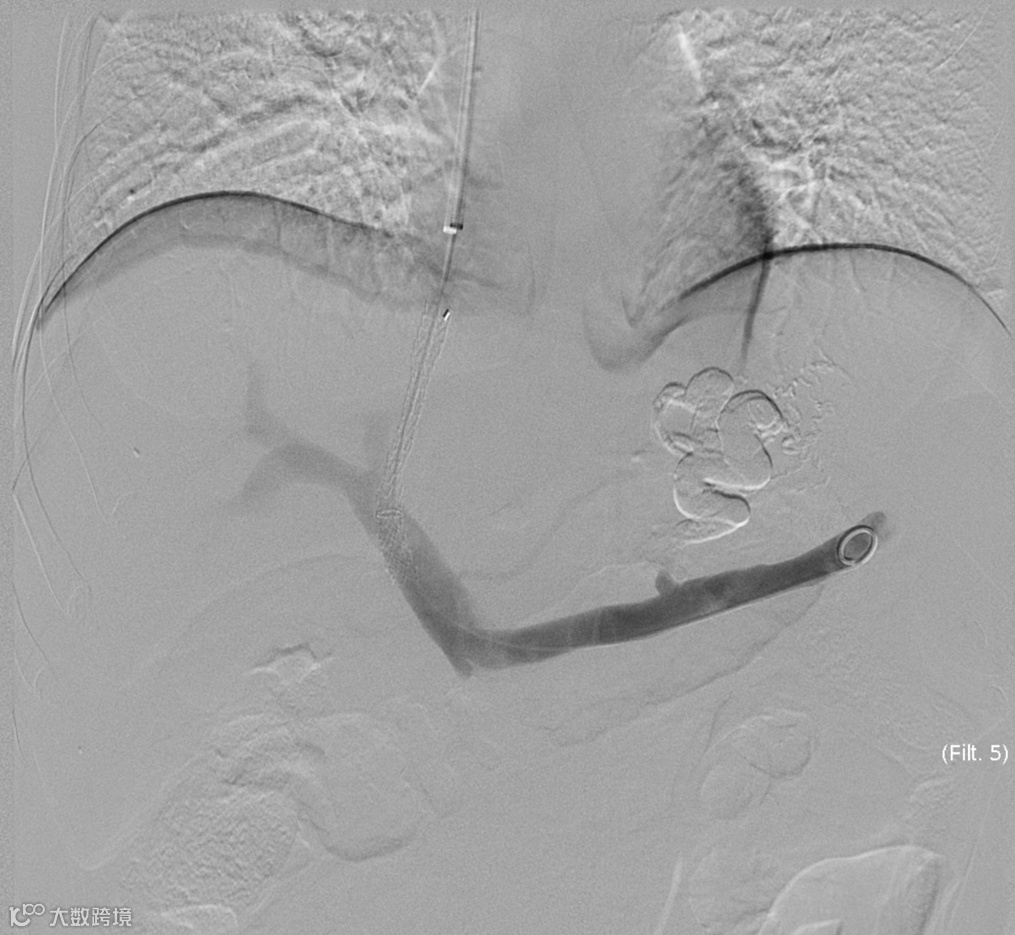

经右颈内静脉穿刺门静脉右支后行造影

超选择插入至曲张静脉,注入弹簧圈栓塞

超选择插入至曲张静脉,经微导管注入格鲁巴胶至曲张静脉血流基本停滞

术后造影(即刻效果):曲张静脉血管网未见显影